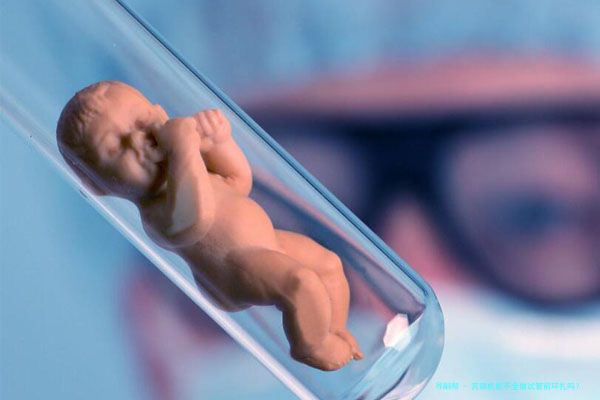

试管婴儿技术已然成为帮助不孕不育病人完成生育愿望的重要手段,但对对于一些存留宫颈性能不全的女性来讲,试管婴儿的成功率会受到影响,以致可能导致早产。宫颈机能不全是指宫颈在妊娠期间提前扩展或开张,导致胎膜早破、羊水的流动失,最终导致早产。这种情况时常发生在妊娠中期对母婴健康致使极大的要挟。所以关于存在宫颈机能不全的女性,在进行试管婴儿之前,需要进行全方位的评介,并采用与之相应的步伐来减少小产风险,提高试管婴儿的成功率。本文将环绕宫颈功能不全做试管前环扎吗?这一问题铺开会商,并详尽阐述宫颈机能不全与试管婴儿的关联、环扎手术的必要性和相关注意事项。

试管婴儿技术虽然能够帮助不孕不育患者达成生育愿望,但关于存在宫颈功能不全的女性来讲,试管婴儿的成功率会受到影响,甚至可能导致早产。这便是因为,宫颈机能不全会导致胚胎着床后更易于发生胎膜早破、羊流水失等情况,进而导致妊娠失利要么早产。